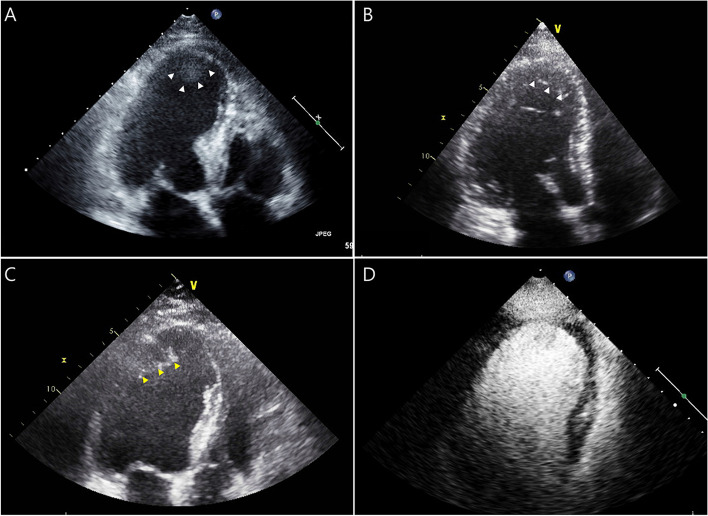

Efficacy of routine contrast echocardiography for the detection of left ventricular thrombus in patients with anterior ST-elevation myocardial infarction.

常规造影剂超声心动图检测前 ST 段抬高型心肌梗死患者左心室血栓的疗效。